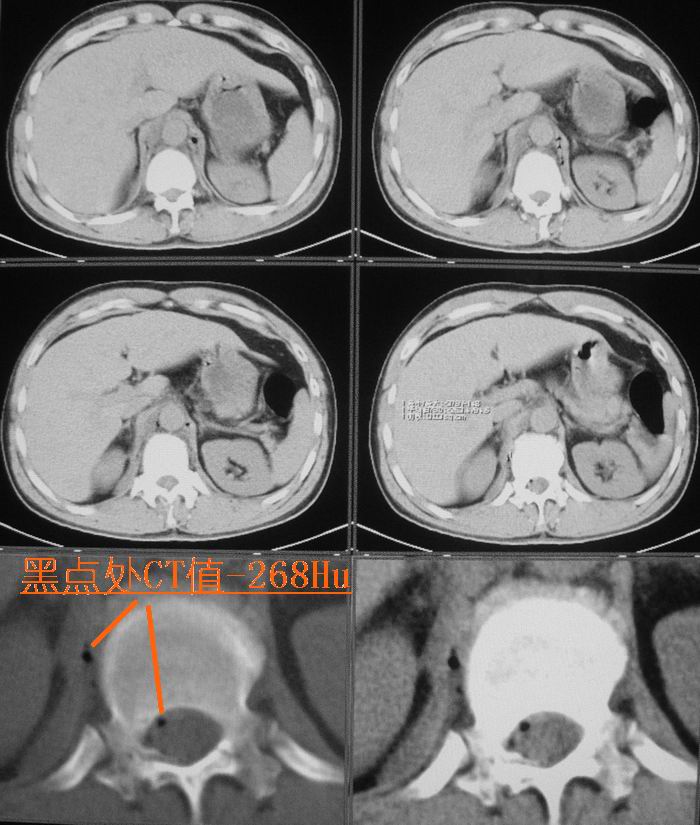

男性,47岁,车祸致胸痛2小时。

请大家看看后纵隔食道及降主动脉周围的软组织密度灶是什么?双侧膈肌脚内侧及椎管内的气体影是怎么回事?

结合病史多考虑纵隔血肿形成 ,椎管及右侧腰大肌内侧气体影也与外伤有关。

要不要考虑食道中下段的损伤呢?这样血肿和气体影就都好解释了。